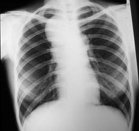

Anti-aging developments - 6 October 2011 -- World COPD Day is a global effort to expand understanding of chronic obstructive pulmonary disease (COPD) and advocate for better care for patients. In 2004, 64 million people had the illness and WHO predicts that COPD will become the third leading cause of death worldwide by 2030. Key risk factors for COPD are tobacco smoking, indoor and outdoor air pollution, and exposure to occupational dusts and chemicals.

Organized by the Global Initiative for Chronic Obstructive Lung Disease (GOLD), the Day is marked by activities implemented by health care professionals and patient groups throughout the world.